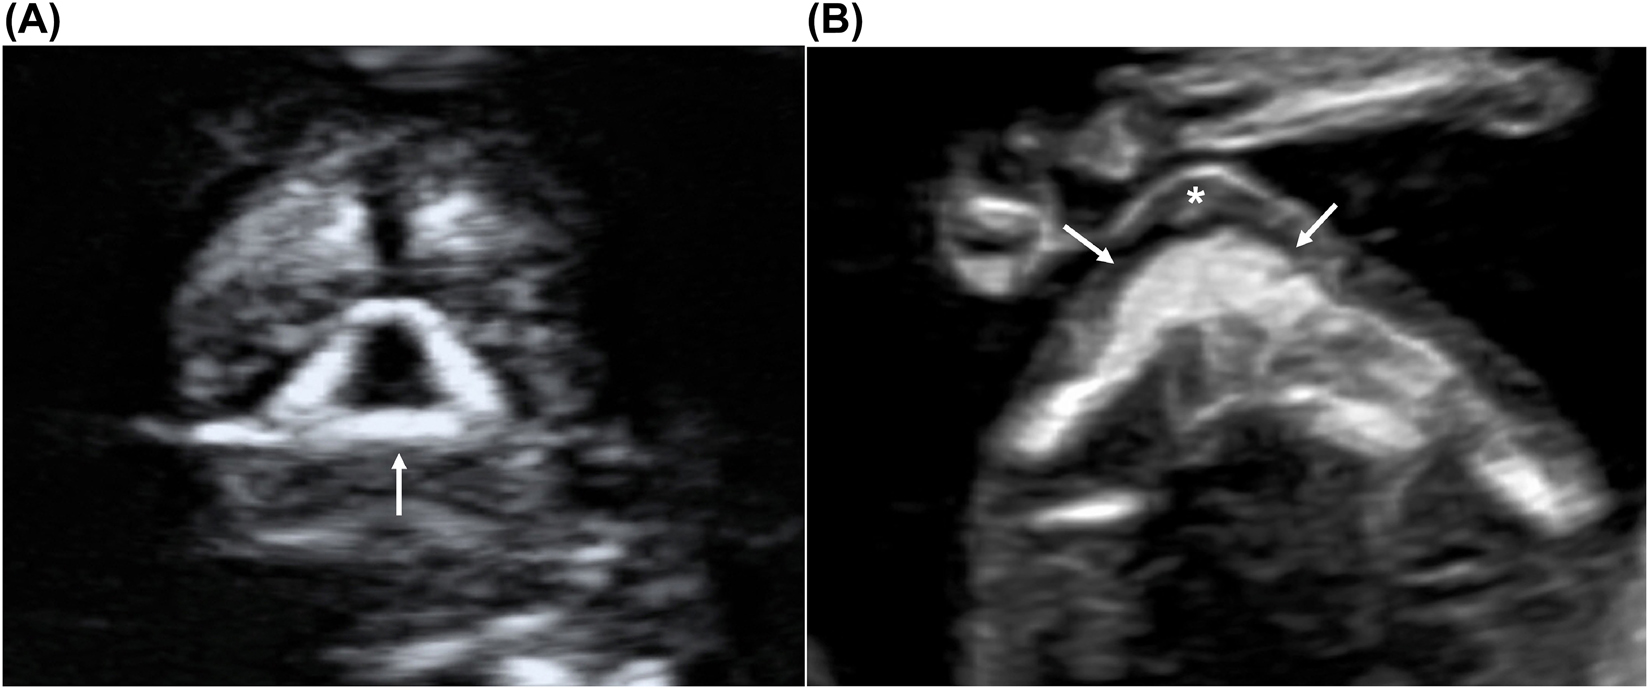

Under normal conditions, the fetal skull appears as an oval-shaped hyperechoic bony structure. The two hemispheres, similar in size, are separated by a straight, uninterrupted midline echo (interhemispheric fissure) on the axial planes. The choroid plexuses should fill the two lateral ventricles on the sides of the midline (butterfly sign on axial view [62]) occupying roughly half or more of the ventricle length/area [63,64] (Figure 1). On the midsagittal view, the anechoic round-shaped diencephalon is visible in the middle of the fetal brain, and the cranial posterior fossa (CPF) structures are just posterior to it, including the brainstem (BS), the 4th ventricle (4V), and the cisterna magna (CM), appearing as three anechoic spaces, roughly similar in size (Figure 2). The biparietal diameter (BPD) could be measured on the axial view in selected cases, mainly for dating purposes.

Midsagittal view of the fetal head and brain.

It is possible to visualize the diencephalon (D) and the cranial posterior fossa structures, including the brainstem (BS), the 4th ventricle (4V), and the cisterna magna (*) appearing as three anechoic spaces, roughly similar in size. The nuchal translucency (NT) is also visible as a fluid space behind the fetal neck. The fetal profile is well visible on this view, including the forehead (F), the nose (N), lips (L) and chin (C).

The cranial posterior fossa should be evaluated routinely on the midsagittal plane, showing three distinguished anechoic spaces similar in size. The measurement of the ratio between the width of the brainstem and the space behind it (BS/BSOB – [36]) is not recommended on a routine basis but could be helpful when the three spaces seem abnormal.

An anterior approach could obtain the midsagittal view of the fetal head (Figure 2), with the ultrasound beam encountering the fetal face before reaching the intracranial structures. To be correctly midsagittal, the fetal profile should be visible, including forehead, nose (bone, overlying skin, and tip), rectangular-shaped palate, diencephalon, and anechoic structures in posterior fossa (BS, 4V and CM). In addition, on a proper midsagittal plane, the bony process above the palate (zygomatic process of the maxilla) should not be visible. The nuchal translucency should be measured on this plane when the ultrasound beam is perpendicular to its lines.